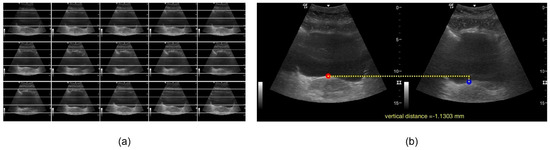

2.3. Data Processing